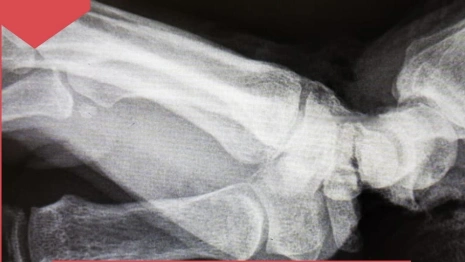

Пострадавшую доставили в травмцентр БСП. Сосуды, нервы, сухожилия и основная часть мягких тканей были отсечены.

В ПИМУ сразу же провели операцию по восстановлению кисти. Конечность удалось спасти. Женщину уже выписали. Ей предстоит длительное восстановление.